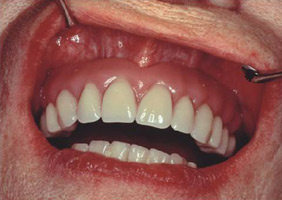

poslije